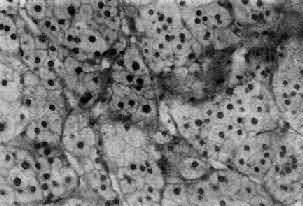

嗜铬细胞瘤(phenochromocytoma) 80%~90%发生于肾上腺髓质,绝大部分为单侧单发性,偶尔见于双侧,90%为良性,好发于30~50岁。肿瘤细胞可分泌去甲肾上腺素和肾上腺素,以去甲肾上腺素为主,偶尔也分泌多巴胺及其他激素,故临床主要有儿茶酚胺过高的症状,表现为血压增高,多呈间歇性发作,并伴有头痛、发汗、末梢血管收缩、脉搏加快、血糖增高、基础代谢上升等症状。肉眼观,大小不一,平均100g左右,甚至可达2000g,有包膜,切面灰红色、灰褐色,常见出血、坏死、囊性变及坏死灶。镜下嗜铬细胞为大多角形细胞,形成细胞索或细胞巢,可有不同程度的多形性,有时出现巨细胞,瘤细胞胞浆内有大量嗜铬的微细颗粒;电镜下,颗粒有包膜,电子致密度低者含有肾上腺素,而包膜不清楚电子致密度高者含有去甲肾上腺素,用免疫组化方法亦可显示。间质主要是血窦。良、恶性肿瘤在细胞形态方面无截然界限,包膜被侵犯並不能作为恶性的肯定证据,但如有周围组织浸润及转移,则属恶性无疑。